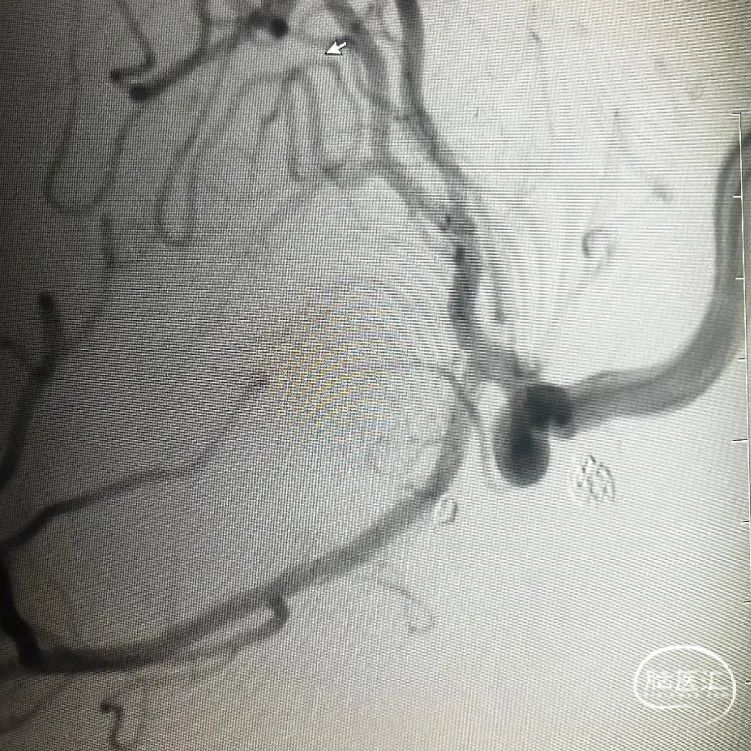

左侧大脑前动脉动脉瘤DSA正侧位

基底动脉尖动脉瘤DSA正侧位

术后即刻影像

基底动脉尖动脉瘤栓塞采用导管平行技术,栓塞用微导管先置入动脉瘤腔内,再通过支架导管从左侧大脑后动脉P1段开始缓慢释放颅内支架至基底动脉中段并充分打开,然后通过预置于动脉瘤腔内的微导管致密栓塞动脉瘤。

左侧大脑前动脉A1段动脉瘤栓塞采用穿网眼技术,首先将支架充分释放并妥善覆盖动脉瘤颈部,然后用以微导丝导引微导管穿过支架网眼进入动脉瘤腔内并致密栓塞动脉瘤。